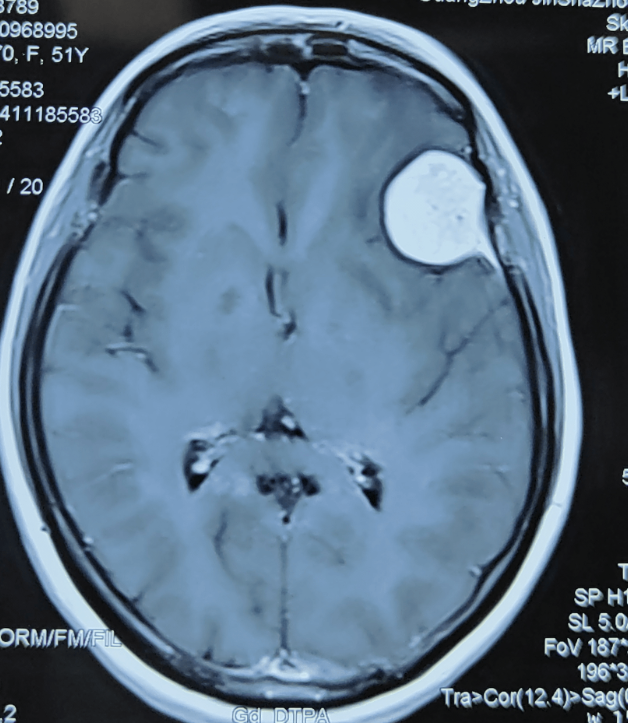

入院后,戴姐做了一系列檢查。確診為顱內占位性病與左側面神經麻痹儀。器屏幕中,只見戴姐的腦膜里,赫然橫亙著一塊像雞蛋般大的“攔路石”一個腫瘤,唐運林教授結合多年的診療經驗,告知她腫瘤及感染侵犯的范圍十分巨大,上至額竇、顱底,下至軟腭、牙齒;腫瘤引起的缺損在顏面部還超過了面中線,在這個范圍內存在大量十分重要的血管、神經及器官,術中稍有不慎,就會引起不可挽回損害,甚至有很大的生命危險。

戴姐的顱內占位性病就是俗稱的腦膜血管球瘤,是血管性腫瘤,呈球形或結節(jié)性生長,由于腫瘤組織供血豐富,局部解剖復雜,給手術切除增加了難度。在門診常常對該疾病的漏診與誤診,導致多數患者長期得不到正確治療,面孔恐怖,痛苦異常,嚴重影響工作和生活。